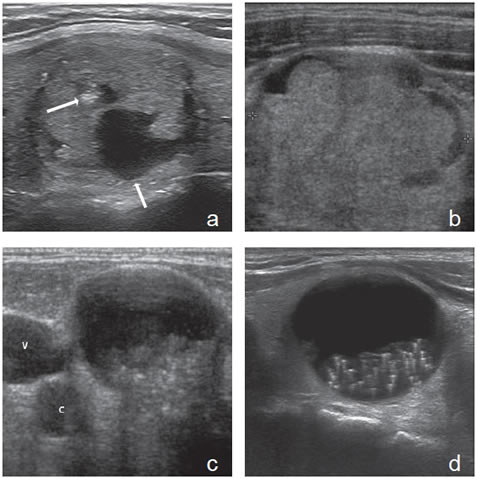

Un nódulo que tiene un componente quístico significativo, usualmente es un nódulo benigno hiperplástico, que ha acumulado abundante coloide (Figura 2a) o bien, un nódulo sólido que ha experimentado un proceso de degeneración colicuativa o hemorragia (Figura 2b). El coloide o el contenido líquido de un nódulo se ve anecogénico (negro en la imagen ecográfica) y las estructuras sólidas se ven ecogénicas (distintos tonos de grises), siendo la ecogenicidad similar al del parénquima tiroideo. En un nódulo sólido la ecoestructura y la ecogenicidad pueden ser variables. En general, la frecuencia de carcinoma es muy baja en nódulos quísticos13 y la mayoría de los carcinomas se presentan como nódulos sólidos (Figura 2c).

Figura 2. a) Quiste coloideo anecogénico y focos ecogénicos (flecha) con artefacto en cola de cometa; b) Nódulo mixto sólido-quístico (cabezas de flechas). Imagen vegetante (flecha) adherida a un tabique que se proyecta al lumen; c) Comparación entre el aspecto ecográfico de un cáncer papilar sólido (flecha abierta) y un quiste coloideo anecogénico.

El parénquima tiroideo normal es de mayor ecogenicidad que los músculos pre-tiroideos. Los nódulos tiroideos pueden ser de menor ecogenicidad que el tejido glandular (hipoecogénicos), de ecogenicidad similar (isoecogénicos) o de mayor ecogenicidad (hiperecogénicos). La ecogenicidad de un nódulo se refiere al nivel de blanco, gris y negro que muestran en la imagen ecográfica (Figura 3a, b y c). La mayoría de los carcinomas papilares (75%-85%) son hipoecogénicos13. La hipoecogenicidad es un signo sensible pero inespecífico, ya que un 30% a 50% de los nódulos benignos14 también son hipoecogenicos (Figura 4). Sin embargo, si la hipoecogenicidad es acentuada (menor que la de los músculos pretiroideos), aumenta la sospecha de carcinoma (Figura 5). Los nódulos hiperecogénicos o isoecogenicos tienen mayor grado de asociación con lesiones hiperplásticas o foliculares benignas, y en mucho menor proporción con el cáncer papilar. Los nódulos puramente quísticos se definen como anecogénicos independiente de si muestran uno que otro fino septo aislado. Cuando el coloide se espesa, se forman microcristales que se ven como focos hiperecogénicos que contrastan con el fondo de coloide anecogénico, y generan un artefacto ultrasonográfico por reverberación, que produce una imagen posterior similar a la cola de un cometa (Figura 2a). La presencia de estos focos hiperecogénicos en un nódulo quístico indican la presencia de abundante coloide y se correlaciona con benignidad; prácticamente están ausentes en un nódulo maligno15.